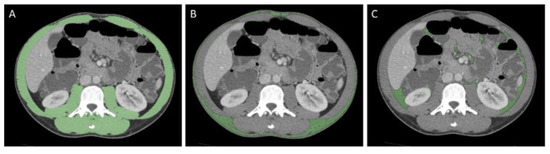

2.3. Image Analysis